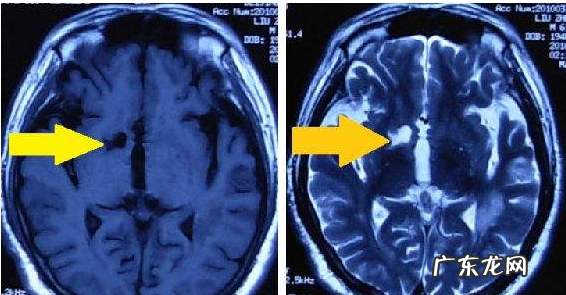

短T1长T2是指在做磁共振检查时在T1序列和T2序列显示病灶的信号,短T1是高信号呈白色,长T2也是高信号呈白色 。比如脑出血8天-4周时,血肿磁共振影像表现就是短T1长T2信号,但是脑出血超急性期(即出血24小时内)和慢性期(病程4周以上),血肿则是长T1长T2信号 。